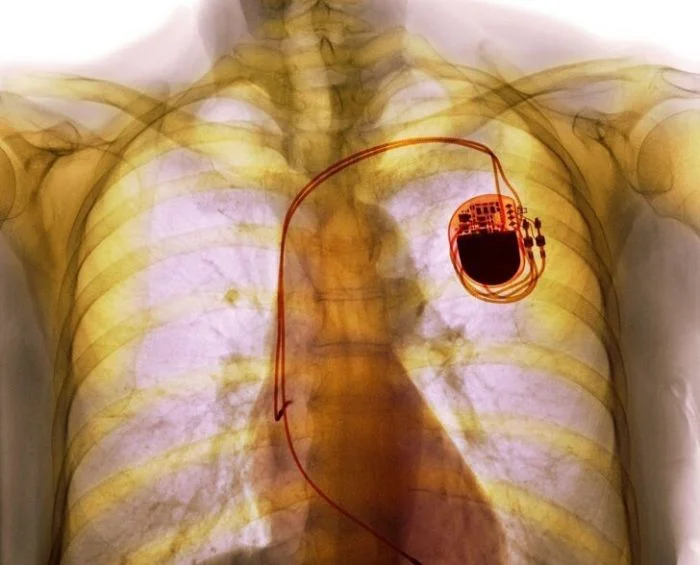

Кардиостимулятор на рентгене